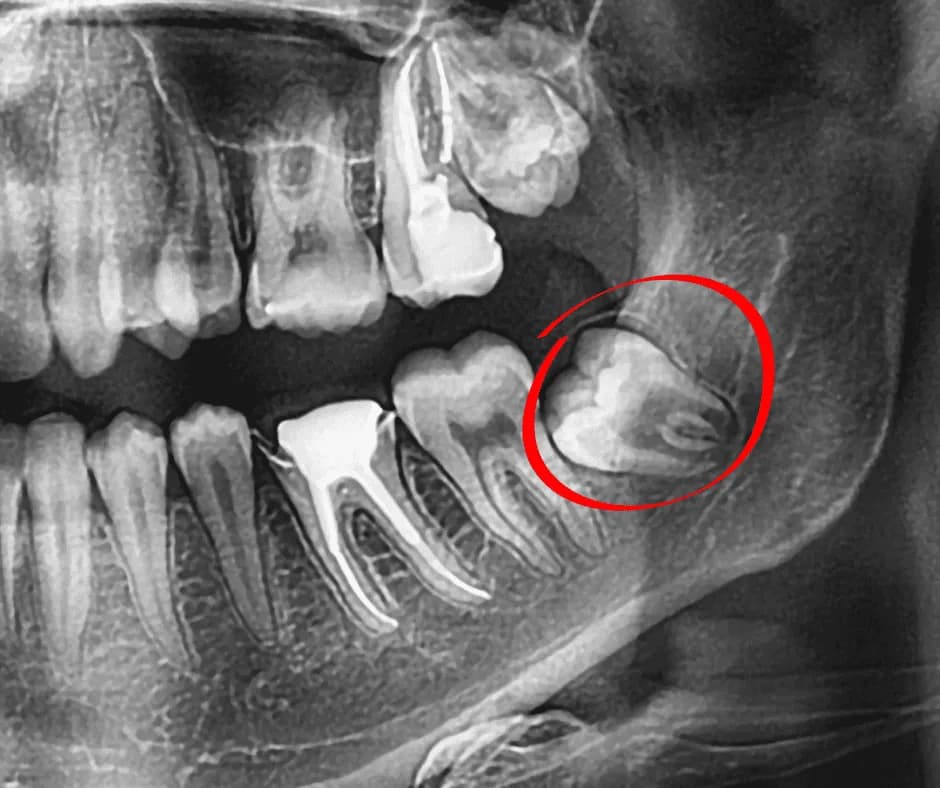

La extracción de cordales o muelas del juicio se recomienda cuando hay dolor, infecciones recurrentes, apiñamiento dental, caries difíciles de tratar o cordales retenidas. En nuestro consultorio en Surco realizamos una evaluación clínica con radiografías para determinar si la extracción es necesaria y el momento ideal para realizarla.